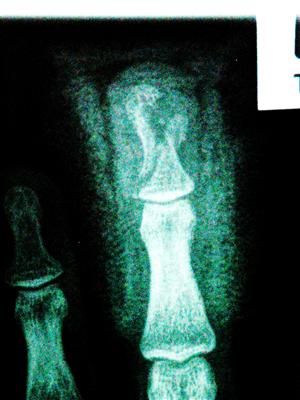

X-ray of break from above. Gap is where hole in my finger was